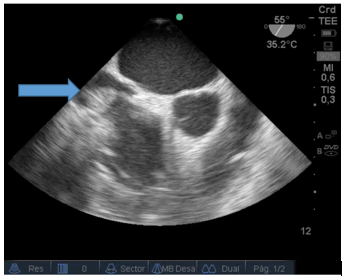

Durante el intraoperatorio, posterior al desclampeo, el paciente sufre descompensación hemodinámica aguda, con severa hipotensión y bradicardia extrema. En ese momento no se presentaban alteraciones metabólicas significativas en los estudios de laboratorio. Se comenzó con maniobras de reanimación cardiopulmonar avanzadas y se colocó ETE mediante el cual se pudo determinar la causa: trombosis masiva intracardiaca (TIC). En las siguientes imágenes se puede observar un trombo proveniente de vena cava inferior y además un cable de marcapaso situado en aurícula derecha. Figura 2.

Figura 2: Vista a 55 grados medio-esofágica: Imagen hiperdensa (flecha) de un gran trombo ingresando desde la vena cava inferior hacia la aurícula derecha